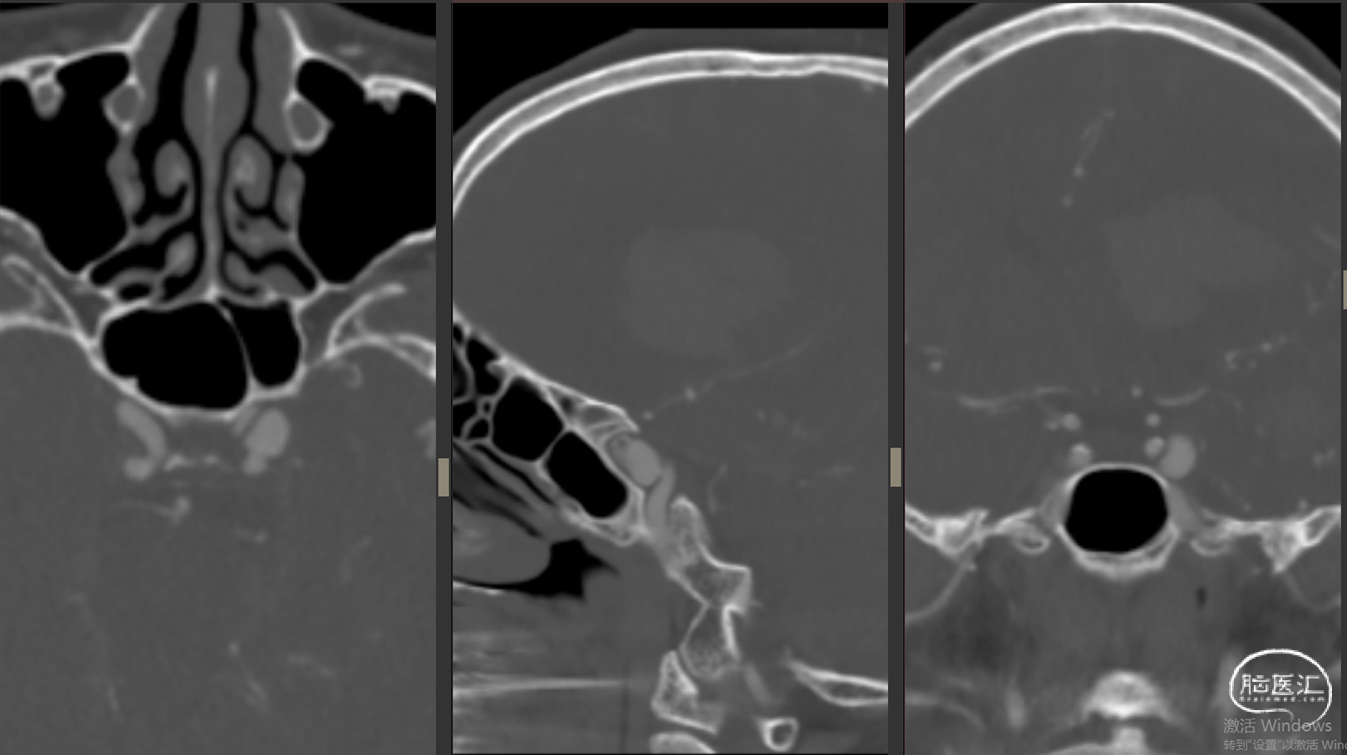

现病史:12小时前无明显诱因突发出现右侧肢体无力,伴言语不能,伴呕吐胃内容物3次,无人事不省,无肢体抽搐,无发热等。就诊当地医院,急查头颅CT示:“颅内出血”,予对症处理后转诊我院。我院急诊查头颅CTA示:“左侧基底节区及左侧额颞叶血肿伴大脑镰下疝、颞叶钩回疝及海马旁回疝可能,左侧颈内动脉C4段所见,考虑多发动脉瘤伴血管畸形,建议DSA检查”。

影像资料:CT、CTA

1.左侧基底节区及左侧额颞叶血肿 2.左侧颈内动脉C4段多发动脉瘤 3.左侧额颞叶血管动静脉畸形

2. 左侧颈内C4段动脉瘤破裂致颈内动脉海绵窦瘘(Barrow A型)

精确诊断:左侧颈内C4段动脉瘤破裂至大脑中浅静脉致左侧基底节区及左侧额颞叶静脉性梗死并出血转化。